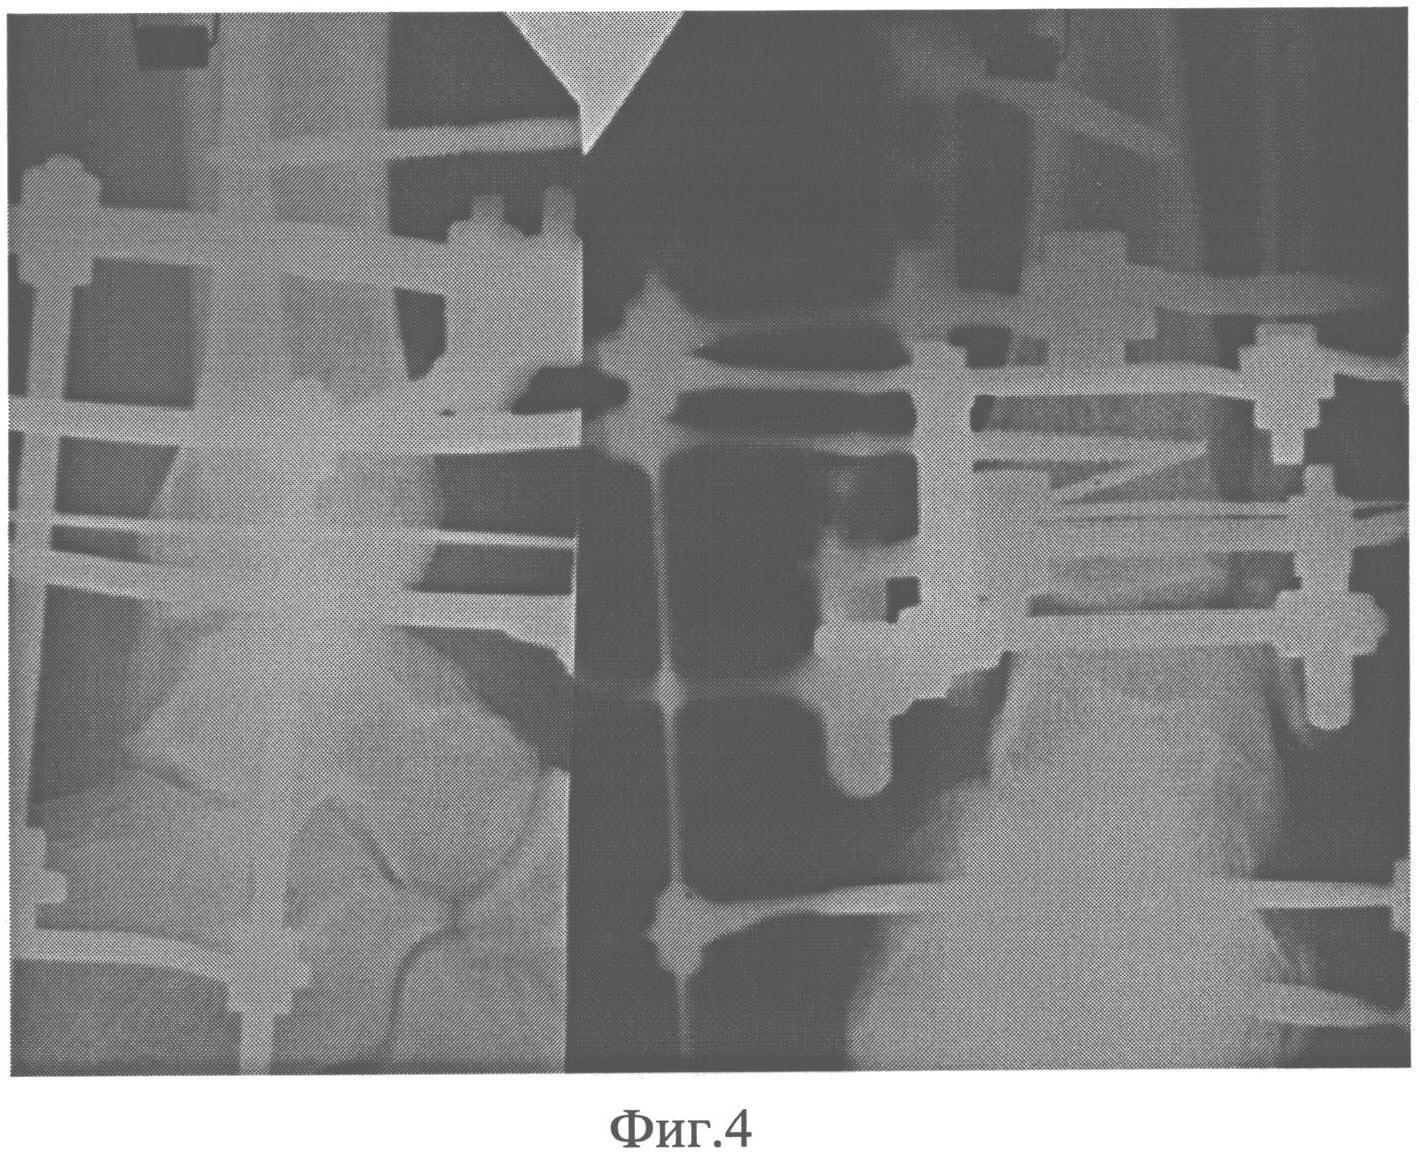

Известно, что в нормально функционирующей нижней конечности имеет место наружная торсия костей голени на величину 18-25°, при этом наружная лодыжка располагается несколько кзади, а внутренняя - выдвигается кпереди от фронтальной оси. При переломе происходит нарушение напряженного состояния в дистальных отделах костей голени с раскручиванием (деторсией) костей кнутри. При этом малоберцовая кость смещается кзади и кнаружи, нередко с «запрокидыванием кзади» дистального отломка (фиг.1).

на фиг.1 показано смещение кзади и кнаружи, с «запрокидыванием кзади», дистального отломка малоберцовой кости при переломе;